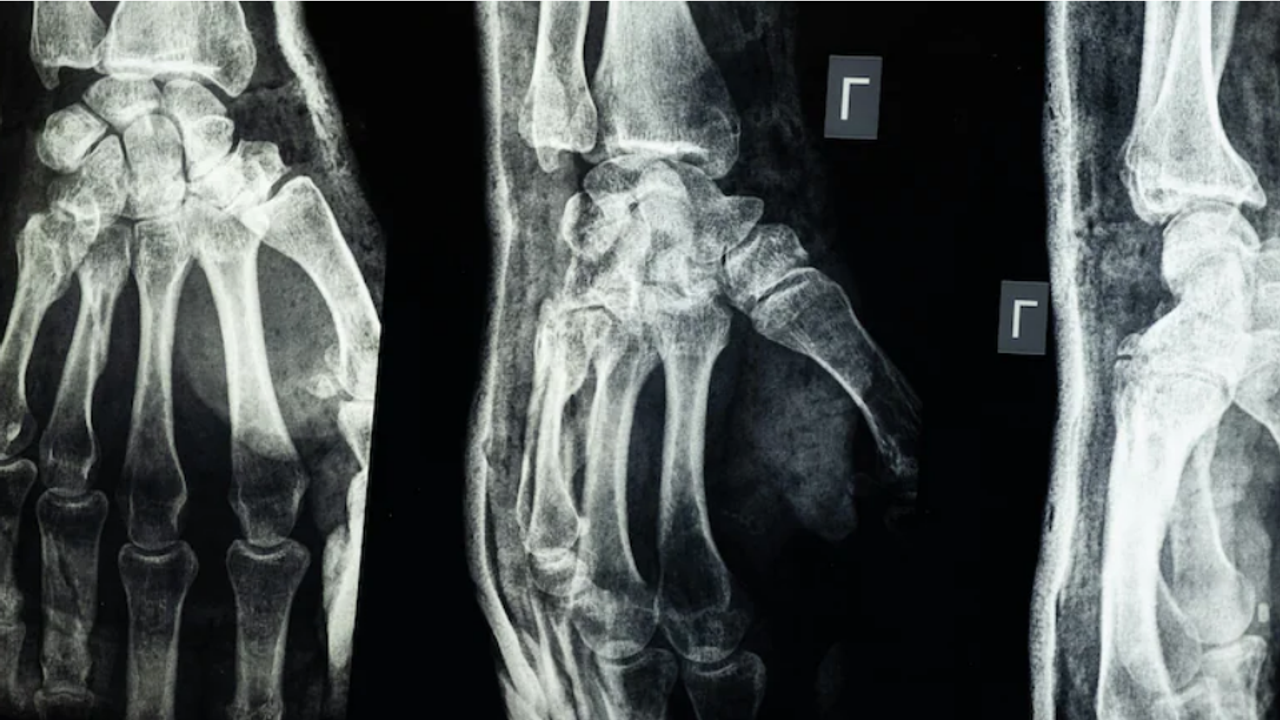

Laboratuvar testleri, “Bone-02”nin hem güvenlik hem de etkinlik açısından başarılı olduğunu ortaya koydu. Denemelerden birinde, işlem üç dakikadan kısa sürede tamamlandı; oysa geleneksel tedavi yöntemleri çelik plakalar ve vidaların yerleştirilmesi için geniş bir kesiye ihtiyaç duyuyor. Çin devlet televizyonu CCTV’ye göre bu yapıştırıcı 150’den fazla hastada başarıyla test edildi.

Yapıştırılmış kemiklerde 400 pound’dan fazla bağlanma kuvveti, yaklaşık 0,5 MPa kesme dayanımı ve 10 MPa basınç dayanımı ölçüldü. Bu sonuçlar, ürünün geleneksel metal implantların yerini alma potansiyeline sahip olabileceğini gösteriyor. Ayrıca bilim insanları, yapıştırıcının reaksiyon ve enfeksiyon risklerini azaltabileceğini belirtiyor.